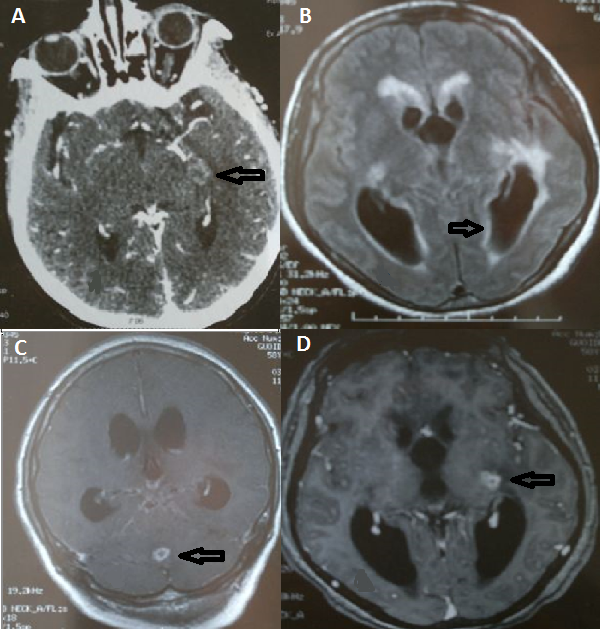

The identification of the cause of acute encephalitis is difficult in spite of many developed diagnosis strategies. The cause is unknown in nearly 30 to 40 % of cases. Tuberculosis is endemic in Tunisia. Tuberculous encephalitis is rare in immunocompetent adults. We report in this work a rare case report of tuberculous encephalitis in an immunocompetent woman. She was 38 years old and had no medical history. She had a clinical presentation of mental confusion and fever that appeared from ten days. She was agitated with neck stiffness. Her initial Glasgow coma scale was thirteen. The CT scan of the head showed a brain temporal abscess (A). The cerebral spinal fluid examination showed elevated proteinorrachia of 172 mg/dl, normal glycorrachia and lymphocytic pleocytosis (76% of 340 WBC/mm3). The Magnetic resonance imaging (MRI) of the head performed in the second day revealed images of hydrocephalus (B). It showed also two images of brain vermian (C) and temporal abscesses (D). The diagnosis of tuberculous encephalitis was made by computing clinical, laboratory and imaging findings. She was admitted in the intensive care unit and treatment by cefotaxim and acyclovir was initiated. Antituberculous drugs were added at the second day of management after MRI. In the sixth day of management, the patient became comatose and required intubation and mechanical ventilation. She died three days later from neurologic complications.